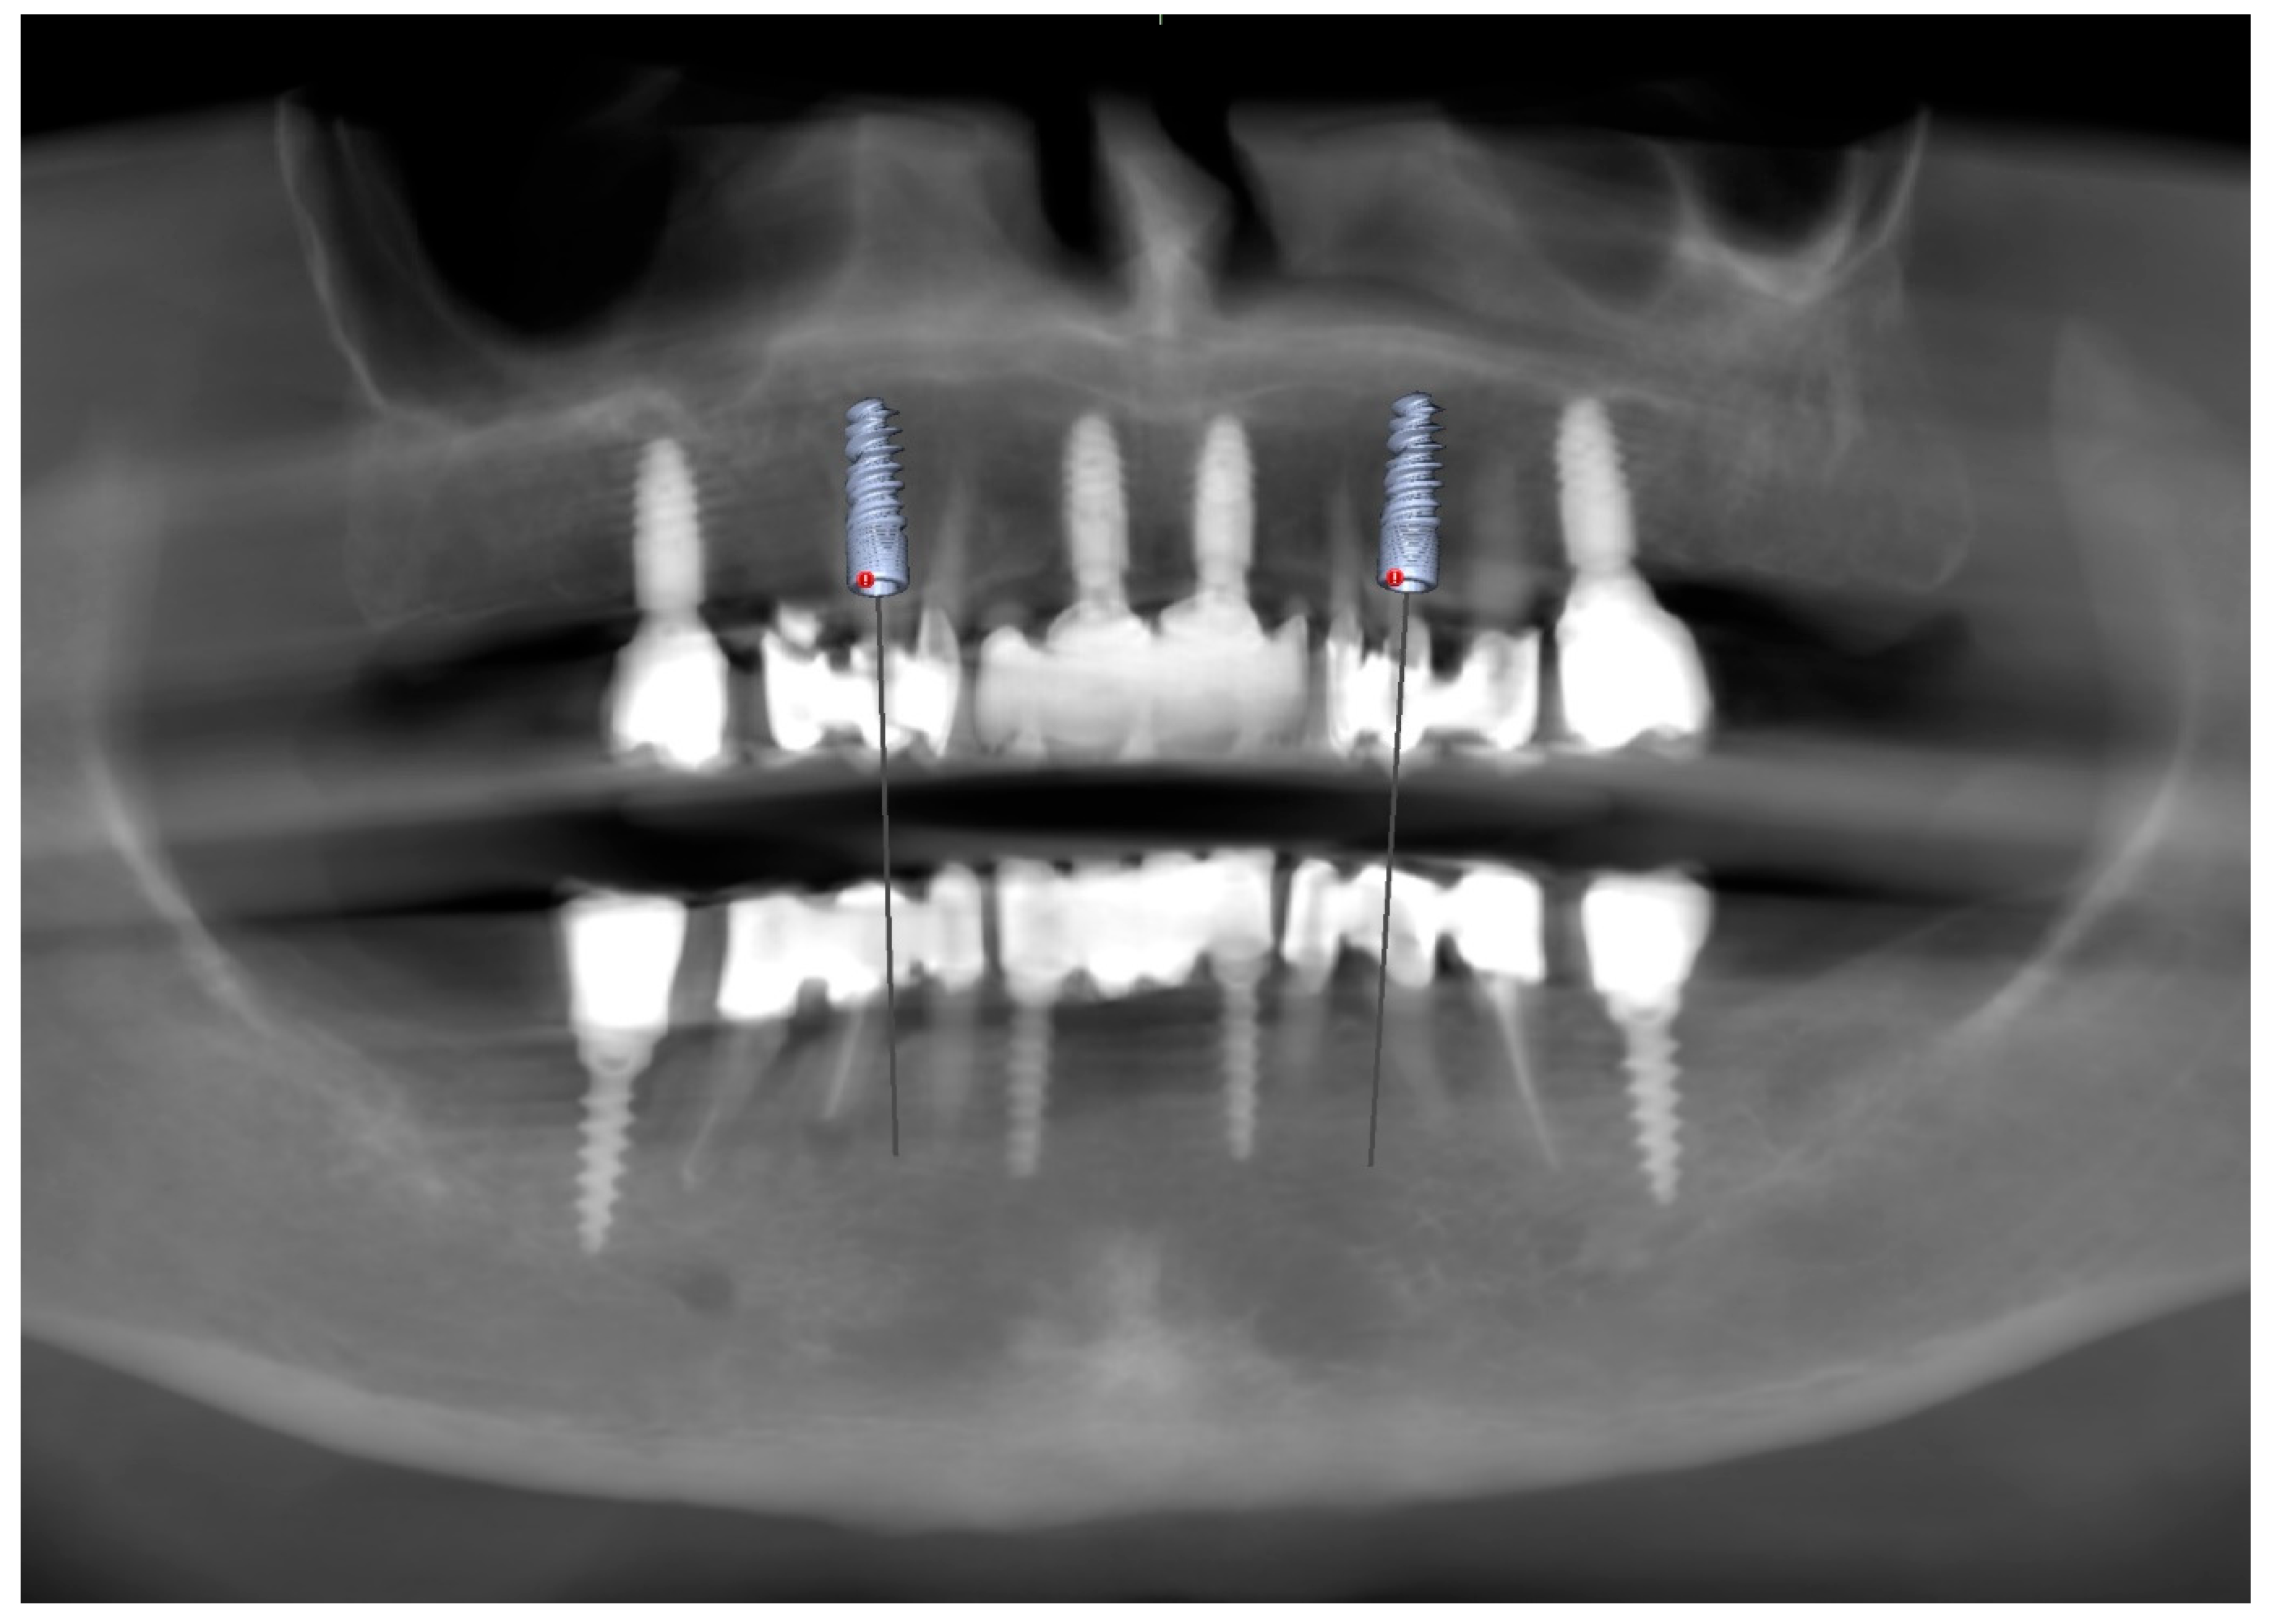

To supplement the clinical findings, a cone beam computed tomography (CBCT) scan was obtained (Figure 1) and evaluated. The implants existing in the maxilla demonstrated proper surrounding bone architecture. The compromised status of the remaining teeth was confirmed. In addition, the available bone conditions in the regions of teeth 14 and 24 were assessed to be adequate for future implant placement, particularly in the context of immediate implant insertion. This is in accordance with the literature emphasising that sufficient bone volume, labial plate integrity, and socket morphology, are critical prerequisites for successful immediate implant placement [7,8,9].

To verify the implant positions and the accuracy of the prosthetic fit, a control CBCT scan was obtained after the delivery of the early provisional restoration. Radiological evaluation confirmed stable positioning of the implants and correct seating of the prosthesis (Figure 11 and Figure 12).

Figure 1. Preoperative panoramic reconstruction from CBCT, showing the initial condition of the existing tooth- and implant-supported restorations in the maxilla and mandible, as well as the visualisation of two planned implants in positions 14 and 24.